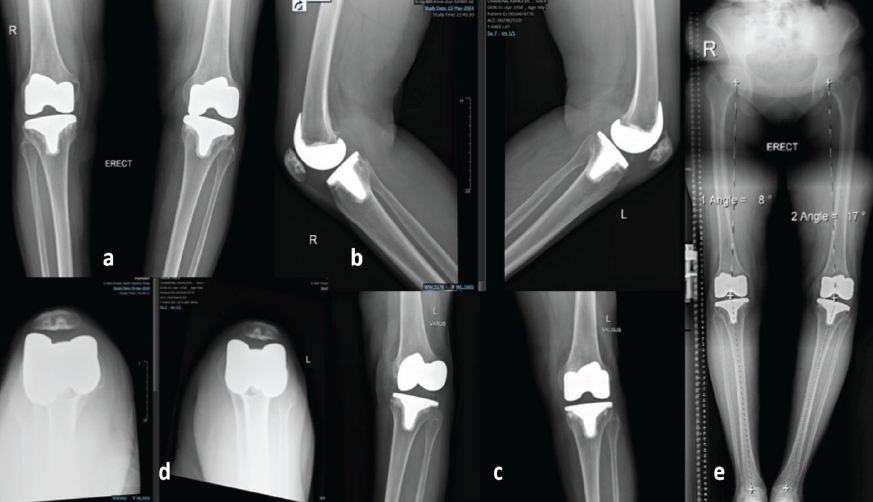

A 60-year-old female presented 1 year following primary TKA (performed elsewhere) with persistent symptomatic instability and functional impairment. Chief complaints included a subjective sensation of “giving way,” difficulty with ambulating long distances, and an inability to climb stairs, which had progressively diminished confidence in the operated limb. These symptoms persisted despite extensive rehabilitation (Fig. 1).

Figure 1: Pre-operative imaging demonstrating features suggestive of posterolateral corner insufficiency following total knee arthroplasty. (a) Anteroposterior radiograph of the knee showing well-fixed femoral and tibial components with preserved medial and lateral joint spaces. (b) Lateral radiograph demonstrating maintained sagittal alignment without evidence of component loosening or subsidence. (c) Varus stress radiograph showing preserved medial compartment stability, valgus stress radiograph demonstrating subtle lateral compartment opening, suggestive of lateral soft-tissue laxity. (d) Skyline view showing patella tracking. (e) Full-length standing scanogram illustrating overall lower limb alignment with residual varus alignment.

On clinical examination, she exhibited a pronounced varus thrust during gait analysis and showed positive dial test at 30° of knee flexion, suggestive of PLRI. Varus laxity was evident on stress testing, and no hyperextension or anteroposterior instability was observed. The rest of her neurovascular examination was unremarkable. Standing long-leg alignment radiographs confirmed well-fixed femoral and tibial components without evidence of loosening. Computed tomography revealed that the angle between posterior condyle line and surgical transepicondylar axis was 4° and thus excluded component rotational malalignment. On X-ray and scanogram analysis, there was a varus of 17° on the affected left side and posterior slope was 3°. Laboratory investigations (C-reactive protein and erythrocyte sedimentation rate) and joint aspiration ruled out infection. Based on the clinical and radiographic findings, a diagnosis of late posterolateral instability secondary to PLC insufficiency was established. Given the well-fixed, well-aligned components, and the absence of infection, a joint-preserving hybrid surgical strategy was planned. The aim was to restore functional stability without revising the components. Under spinal anesthesia, the joint was exposed through a standard medial parapatellar approach. Intraoperative assessment revealed well-fixed and properly positioned components. However, the rotating platform (RP) tibial insert exhibited significant rotational instability, particularly pronounced during application of varus stress and external rotation in mid-flexion. The tibial cut was noted to be in slight varus alignment, a finding suggestive of possibly intraoperative compensation for medial tightness during the index arthroplasty (Fig. 2). Furthermore, the lateral soft-tissue structures, specifically the PLC, demonstrated attenuation with associated functional incompetence, directly contributing to the observed persistent rotatory laxity (Fig. 3 and 4).